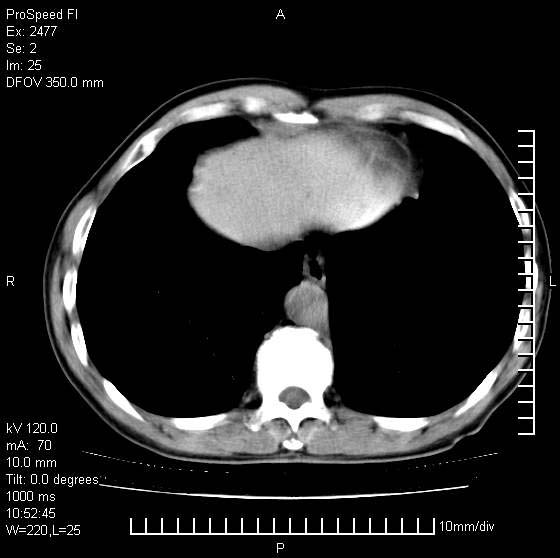

以下是引用天南地北在2007-10-9 14:29:00的发言:[br]1:右上肺结核[br]2:右肺下叶肿块:不支持肺癌,首先考虑炎性病变-肺脓疡可能性大[br]理由:1:临床病史支持,肺脓肿症状不明显应该是不规则服药造成。[br] 2:肿块边缘模糊,周围可见炎性渗出,长毛刺,内见支气管征,不过有点不规则。[br] 我感觉下肺癌这个诊断有点偏左,建议积极抗炎治疗后复查

以下是引用卜一在2007-10-9 15:55:00的发言:[br][br] [br] 1:右上肺结核[br]2:右肺下叶肿块:不支持肺癌,首先考虑炎性病变-肺脓疡可能性大[br]理由:1:临床病史支持,肺脓肿症状不明显应该是不规则服药造成。[br] 2:肿块边缘模糊,周围可见炎性渗出,长毛刺,内见空气支气管征,不过有点不规则。[br] 我感觉下肺癌这个诊断有点偏左,建议积极抗炎治疗后复查![br]支持! [br] [br] [br]

以下是引用wxy7406在2007-10-9 21:02:00的发言:[br]结合临床病史首先考虑感染性病变,但周围型肺癌不能除外,1.患者年龄偏大2.临床有咯血3.(也觉得是最重要的一点)病灶内有偏心性空洞。

以下是引用王仕学在2007-10-9 13:48:00的发言:[br]右下肺周围性肺癌可能性大,最好活检吧

以下是引用hhcckk在2007-10-9 15:18:00的发言:[br]右上肺病灶考虑结核,病灶多种形态并存(纤维化、增殖性病灶并存)[br]右下肺病灶比较难说,个人意见更趋向于“天南地北”的诊断----肺脓肿[br]1、病人有明显的寒战,高热,肿瘤病人很少出现[br]2、病灶周围的肺纹理走向柔和,没有肿瘤病灶常见的集束征[br]3、病灶边缘的毛刺较长,恶性肿瘤多为短毛刺[br]痰中血丝和病人的年龄是两个不利于良性肿块的因素,建议早点活检

以下是引用ydx_74在2007-10-9 15:53:00的发言:[br]右上肺结核,右下中心性肺癌可能大,肺门淋巴结肿大。